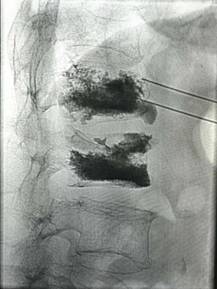

经皮穿刺椎体成形术

优点:微创,迅速解决老年骨质疏松性骨质疼痛。